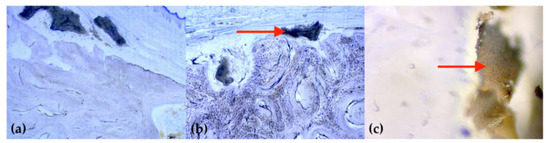

2.3. Histology

- Fischer, K.R.; Stavropoulos, A.; Calvo-Guirado, J.L.; Schneider, D.; Fickl, S. Influence of local administration of pamidronate on extraction socket healing—A histomorphometric proof-of-principle pre-clinical In Vivo evaluation. Clin. Oral Implant. Res. 2015, 26, 1135–1142. [Google Scholar] [CrossRef]

- Cha, J.K.; Sun, Y.K.; Kim, M.J.; Sanz, M.; Jung, U.W. Anti-Resorptive effect of pamidronate on extraction socket wall in dogs. Clin. Oral Implant. Res. 2018, 29, 688–696. [Google Scholar] [CrossRef] [PubMed]

- Saulacic, N.; Muñoz, F.; Kobayashi, E.; Chappuis, V.; Gonzáles-Cantalapiedra, A.; Hofstetter, W. Effects of local application of alendronate on early healing of extraction socket in dogs. Clin. Oral Investig. 2019, 1–11. [Google Scholar] [CrossRef] [PubMed]